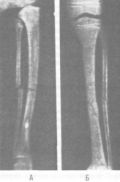

Рис. 49. Рентгеновские снимки перелома костей голени в сагиттальной (слева) и фронтальной (справа) проекциях (по 3. С. Мироновой) |

При осмотре видны припухлость из-за кровоизлияния, искривление или укорочение конечности вследствие смещения отломков. Как правило, наблюдается неестественная подвижность в месте перелома, сопровождающаяся хрустом (крепитация отломков). При открытых переломах отломки кости, повредив мягкие ткани и кожу, выступают из раны. Наиболее точный метод диагностики переломов — рентгенография (рис. 49).

Рис. 49. Рентгеновские снимки перелома костей голени в сагиттальной (слева) и фронтальной (справа) проекциях (по 3. С. Мироновой)